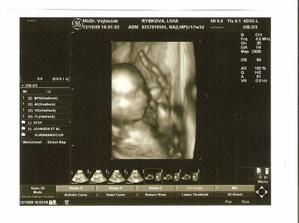

Po roku dlhého skúšania sa nám konečne podarilo...Sme s manželom veľmi šťastní a nevieme sa našeho prvo-rodeného bábatka dočkať.

Pomohol mi určite FEMIBION 800- kyselina listová, ktorú som kúpila na plánované tehotenstvo, a ten malý zázrak sa nám podaril do 2 mesiacov...Určite Vám doporučujem , ktoré máte tiež problém otehotnieť...Ked sa vám s tým do roka nepodarí, tak bude chyba niekde inde.....